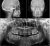

КОМПЛЕКСНЫЙ ГИБРИДНЫЙ КЛКТ ДЛЯ 2D/3D ВИЗУАЛИЗАЦИИ. ИЗОБРАЖЕНИЯ В ВЫСОКОМ РАЗРЕШЕНИИ С ЗАХВАТОМ МЕЛЬЧАЙШИХ ДЕТАЛЕЙ

GIANO HR – универсальное обновляемое устройство от NewTom для всех задач, связанных с радиографией. Благодаря полному диапазону опций 2D и 3D исследования для стоматологии оно предлагает множество особых трехмерных обследований для челюстно-лицевой хирургии, оториноларингологии и осмотра шейного отдела позвоночника. Визуализация только наивысшего качества с технологиями и опытом NewTom

NewTom GiANO HR новейшая модель была официально представлена на международном конгрессе радиологов ECR 2018 в марте в Вене. Благодаря обновленным системам механики и запатентованным механизмам работы аппарат отличается от своих сверстников Высочайшим качеством получаемых изображений, как 2D, так и 3D. Лучшее качество снимков и мы отвечаем за это! Этот аппарат заменит три аппарата! Панорамный аппарат, цефалометрическая приставка и конусно-лучевая компьютерная томография интегрированы в единую платформу. В комплекте детектор для выполнения 3D исследований с захватом области 13х16 см, Сьемный 2D CMOS детектор для выполнения панорамных исследований, и ТРГ.